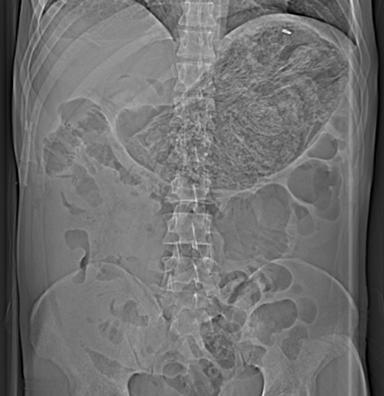

We report the case of a 44-year-old Irish male who presented following ingestion of polyurethane foam. He was asymptomatic on presentation but developed a small bowel obstruction shortly thereafter.

我们报告一例44岁爱尔兰男性因吞食聚氨酯泡沫前来就诊的病例。他就诊时无症状,但随后不久便出现了小肠梗阻。